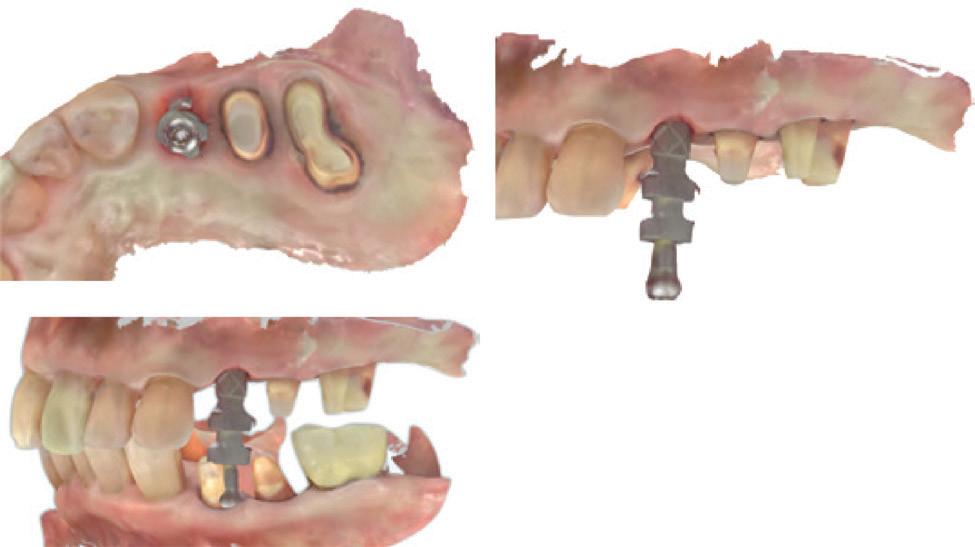

In 1975, one of my patients who was 18 years old became involved in a car accident; he hit the steering wheel with his chin and sustained 2 horizontal fractures in his 31, both quite a way subgingivally. The 41 and 32 were intact. The normal treatment at that time would have required extraction of the 31 and the placement of a partial denture or a bridge to replace the missing tooth.

Knowing that he had nothing to lose, he agreed to let me experiment on him. I extirpated the 31, drilled 10mm past the apex using a sterile Kurer Post spiral drill that matched the diameter of my titanium wire. I sterilised the Titanium using a

Yes, I did stick my neck out, but the result ended being a lot better for the patient than if we had opted for a bridge or a partial denture. The biological cost was negligible and we bought him 30 years of function until a better and more modern treatment became available.

In the current regulatory environment, treatment such as I described is not only illegal and would result in crippling fines being imposed by the TGA, but possibly result in losing one’s right to practice. If I had made a conventional bridge, the teeth either side would have been compromised and possibly lost by now, a partial denture would have caused periodontal problems.